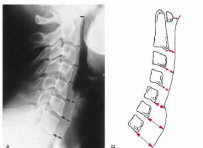

Q what are the names for these measurements? and what is the average + range?

A: Intervertebral Disc Height

assesses the height of the lumbar discs. There are two methods mentioned:

Hurxthal's Method (Right pic.) measures mid-point of body and

Farfan's Method (Left pic.) Uses ratio of anterior (A), Posterior (P) disc heights, and Disc diameter (D).

A/D = Anterior Height Ratio (AHR)

P/D = Posterior Height Ratio (PHR)

Disk height= AHR/PHR.